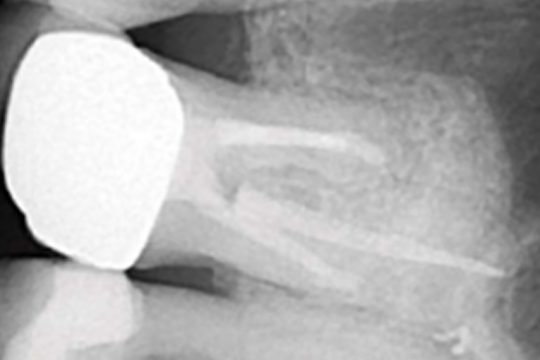

Endodontics

Paradigm Shift in Composite Restorations

Increasing accuracy and efficiency with the Morita X800